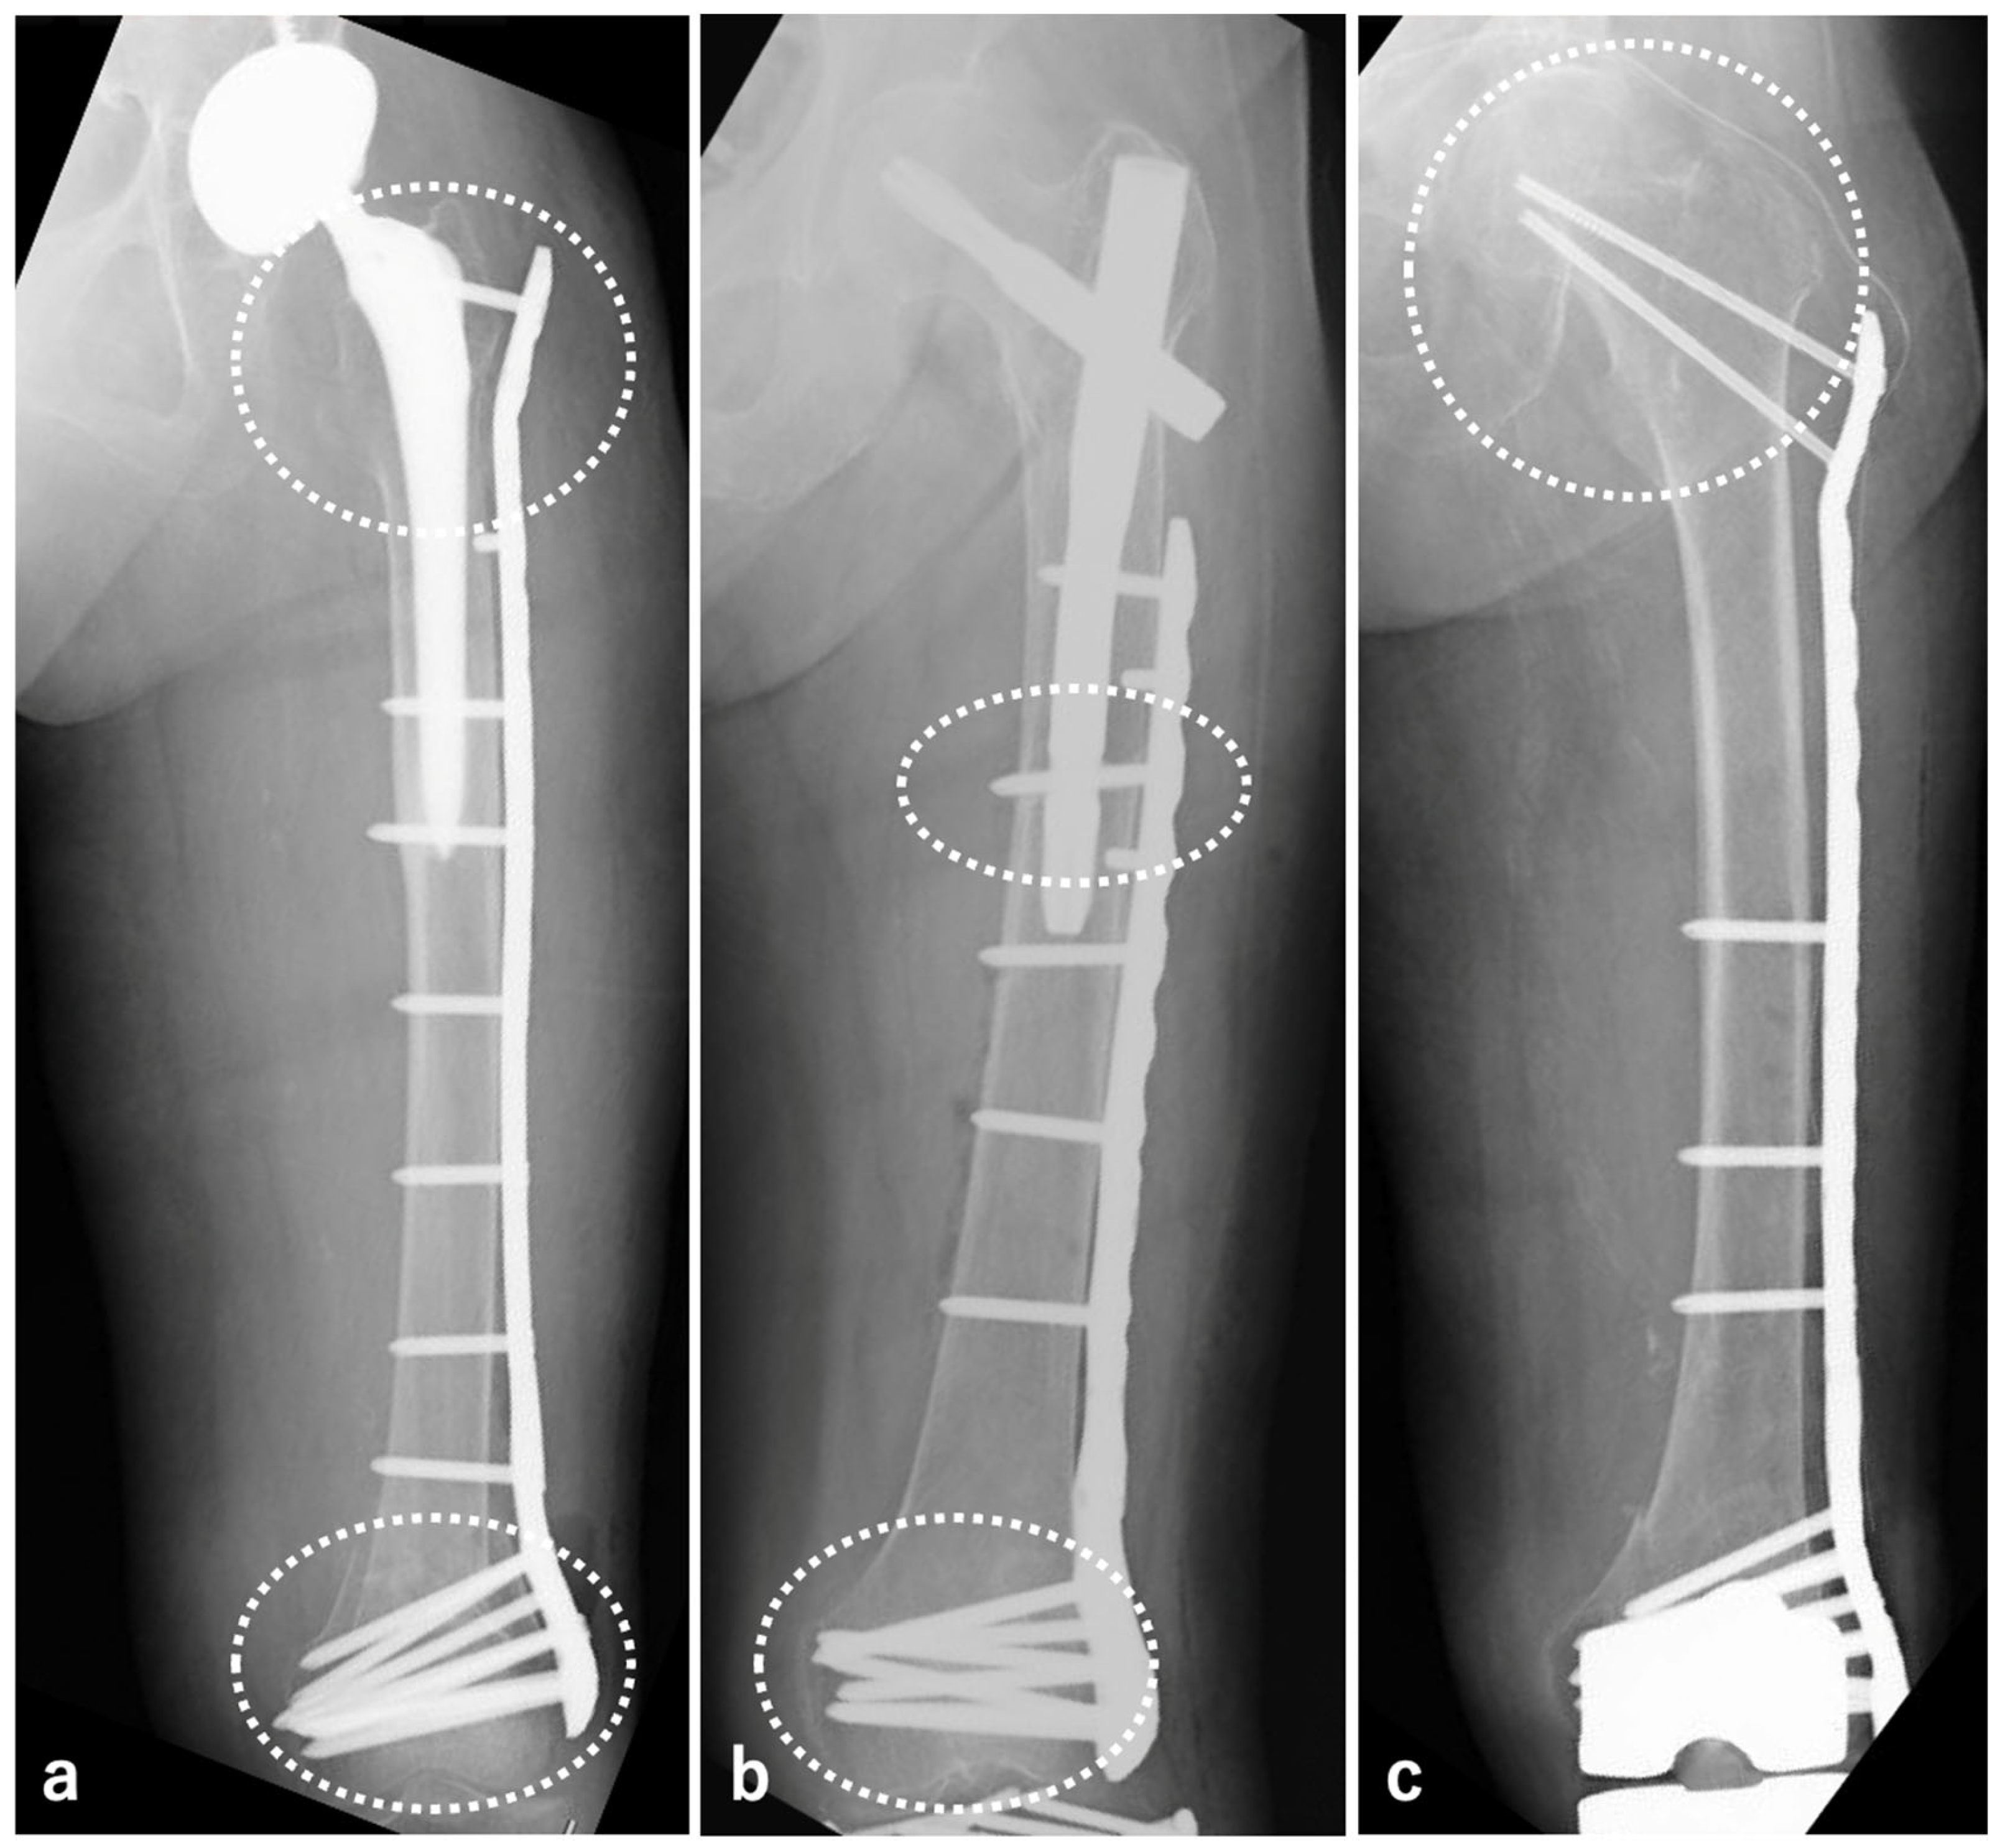

2.3.1. BHA/THA

2.3.2. SFN

2.3.3. TKA

4. Discussion